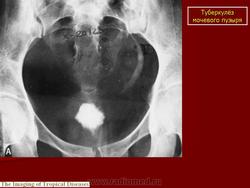

Рентгенологические методы исследования: флюорография (рентгенография) легких, обзорная и внутривенная урография в различных модификациях, томография почек, ретроградная пиелография, цистография, уретроцистопростатография, ангиография и др. Обзорный снимок мочевых путей позволяет обнаружить обызвествления в органах мочеполовой и других систем, изменения опорно-двигательного аппарата (туберкулезный спондилит, метастазы при раке почки и т. п.), определить контуры и размеры почек (увеличение или уменьшение, выбухания, втяжения). По внутривенной урограмме оцениваются функциональное состояние почек и анатомические особенности чашечно-лоханочной системы, мочеточников, мочевого пузыря; урография - основной рентгенологический метод исследования. Соответственно форме и стадии нефротуберкулеза могут быть выявлены; при субклиническом нефротуберкулезе - слабое контрастирование чашечно-лоханочной системы, хаотичное расположение чашечек, их деформация, при папиллите («начальном» деструктивном нефротуберкулезе) - неровность, стушеванность, нечеткость контуров чашечки ввиду наличия признака деструкции, при кавернозном туберкулезе - наличие полостей как в корковом, так и в мозговом слое с неровными, фестончатыми краями; при туберкулезном пионефрозе - изображение увеличенной почки с выбухающими неровными контурами, наличием больших полостей распада, нередко сливающихся между собой, резким снижением либо потерей функции (выключение - аутонефрэктомия); при нефросклерозе (вторично-сморщенная почка) - почка небольших размеров.

Начальный признак специфического поражения мочевых путей - расширение чашечно-лоханочной системы и мочеточника (снижение их сократительной способности в результате токсического воздействия, изменения функционального характера). Во всех случаях «неясной» уретерогидронефротической трансформации врач должен предположить наличие туберкулеза мочевой системы. В дальнейшем обнаруживают различные деформации чашечно-лоханочной системы (с уменьшением ее емкости) с явлениями гидрокаликоза; сужения мочеточника с расширением его выше стеноза; натянутость, четкообразную форму мочеточника; симптом подтянутости стенки мочевого пузыря; уменьшение емкости и различные деформации его контуров вплоть до появления двойного контура - симптома «песочных часов». При восходящей или микционной цистографии, урет-роцистопростатографии выявляют пузырно-мочеточниковый рефлюкс, а при последней - сужения уретры и затекание контрастного вещества в полости предстательной железы. Томографию почек применяют для уточнения контуров почки. Ретроградную пиелографию выполняют при неинформативности внутривенной урографии и для выяснения характера выключения туберкулезного очага (сопоставление пиело- и урографических данных). Ангиография позволяет получить представление об ангиоархитектонике пораженной почки, что важно при определении хирургической тактики.